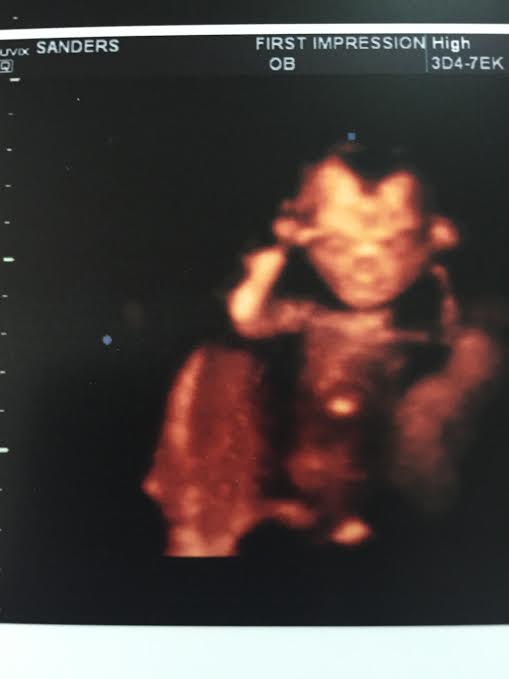

Kevin and I decided to change it up a little bit and do one of the fancy ultrasound places to determine the sex for Father’s Day. Everyone was thinking it’d be mid-July before we knew, so we wanted to really surprise all of the awesome men in our lives with the news.

Holy shit – we’re having a baby girl.

I’ve been consistently measuring 6 days ahead since our 8 week scan and it’s no different now, so I’m thinking we’re looking at more like a Thanksgiving baby and not a December baby!